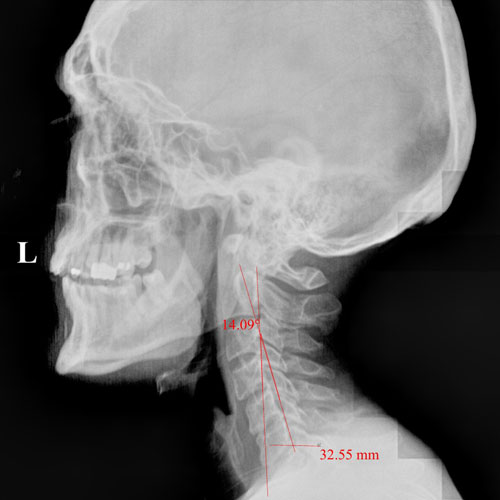

In this case, initial cervical spine X-rays revealed a significant loss of normal neck curvature, a condition that places excessive strain on the spine and nervous system. When the cervical curve is reduced, the head shifts forward, increasing stress on spinal joints, discs, and nerves — often leading to chronic neck pain, headaches, migraines, and neurological symptoms.

Before Chiropractic Treatment: The patient’s X-rays showed a flattened cervical curve, meaning the neck was no longer supporting the head in its ideal position. This type of misalignment is commonly linked to long-term spinal degeneration, nerve irritation, and persistent symptoms that don’t resolve with medication alone.

When spinal structure is compromised, the body is forced to compensate — and over time, those compensations break down.